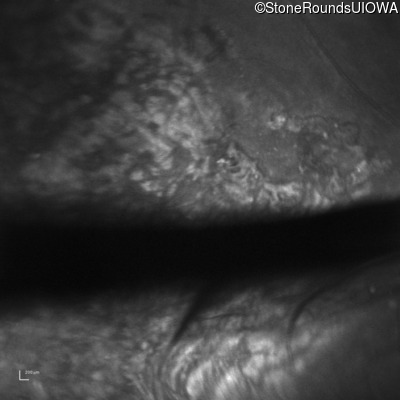

Infrared Fundus Photograph - Right - 20/200 sc

Exemplar